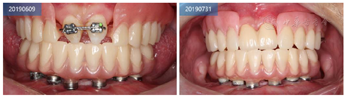

行数字化导板引导的下颌all-on-6种植手术,正畸治疗中切牙,角化龈游离移植,复合基台水平钛支架修复。

安放骨支持式种植导板,在导板引导下用先锋钻在牙槽窝定点和定方向,种植窝直径2.4~2.8mm后停止扩孔,植入Nobel Active 3.5mm×8mm种植体,利用种植体的自攻性到达预定深度,均在骨平面以下,6颗种植体尽量保持在一个平面利于后期修复,所有种植体初期扭矩达到50N/cm,然后平整骨面,安放复合基台(图17)。

2周后行游离龈移植手术,在上颌腭侧左右对称各切取1.5mm牙龈组织,包括角化上皮及其下方少许结缔组织。将游离半厚瓣移植到下颌左右侧前庭沟处,缝合创面(图18)。3周后复查,上颌角化龈缺损区域愈合良好,种植体周围角化龈部分恢复,前庭沟加深,种植体周围软组织移动减少(图19)。